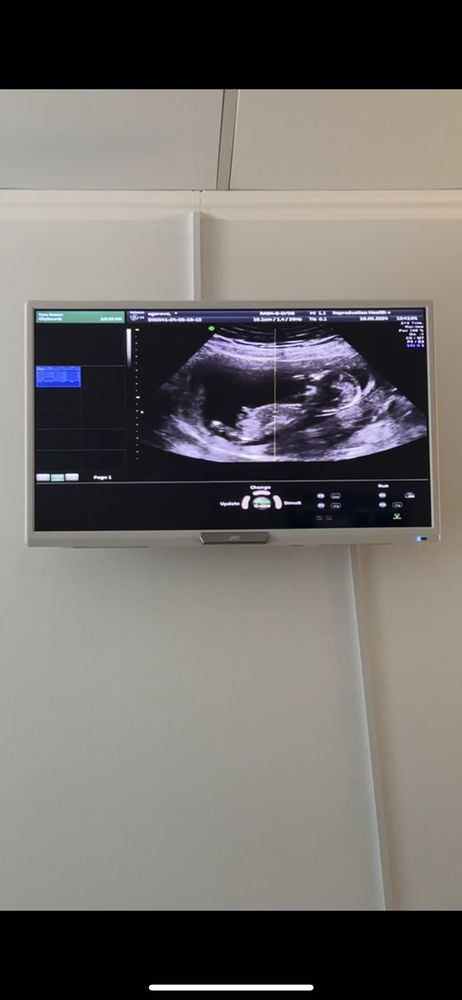

Девочка или мальчик

Наверное, я склоняюсь больше к девочке. Но по данному снимку это больше пальцем в небо. Скажем так, 51% девочка, 49 мальчик)

Склоняюсь к тому, что верхнее это мальчишеский бугорок, а нижнее просто огрехи поплывшей картинки.

Евгения, ну вот нижнее это нога, я несколько раз пересмотрела видео с узи 😅

Дело не в бугорочках, а под каким углом они расположены . На таком сроке это определяет крутой узист!а позже подтверждает. Все остальное - гадалка баба Галя)